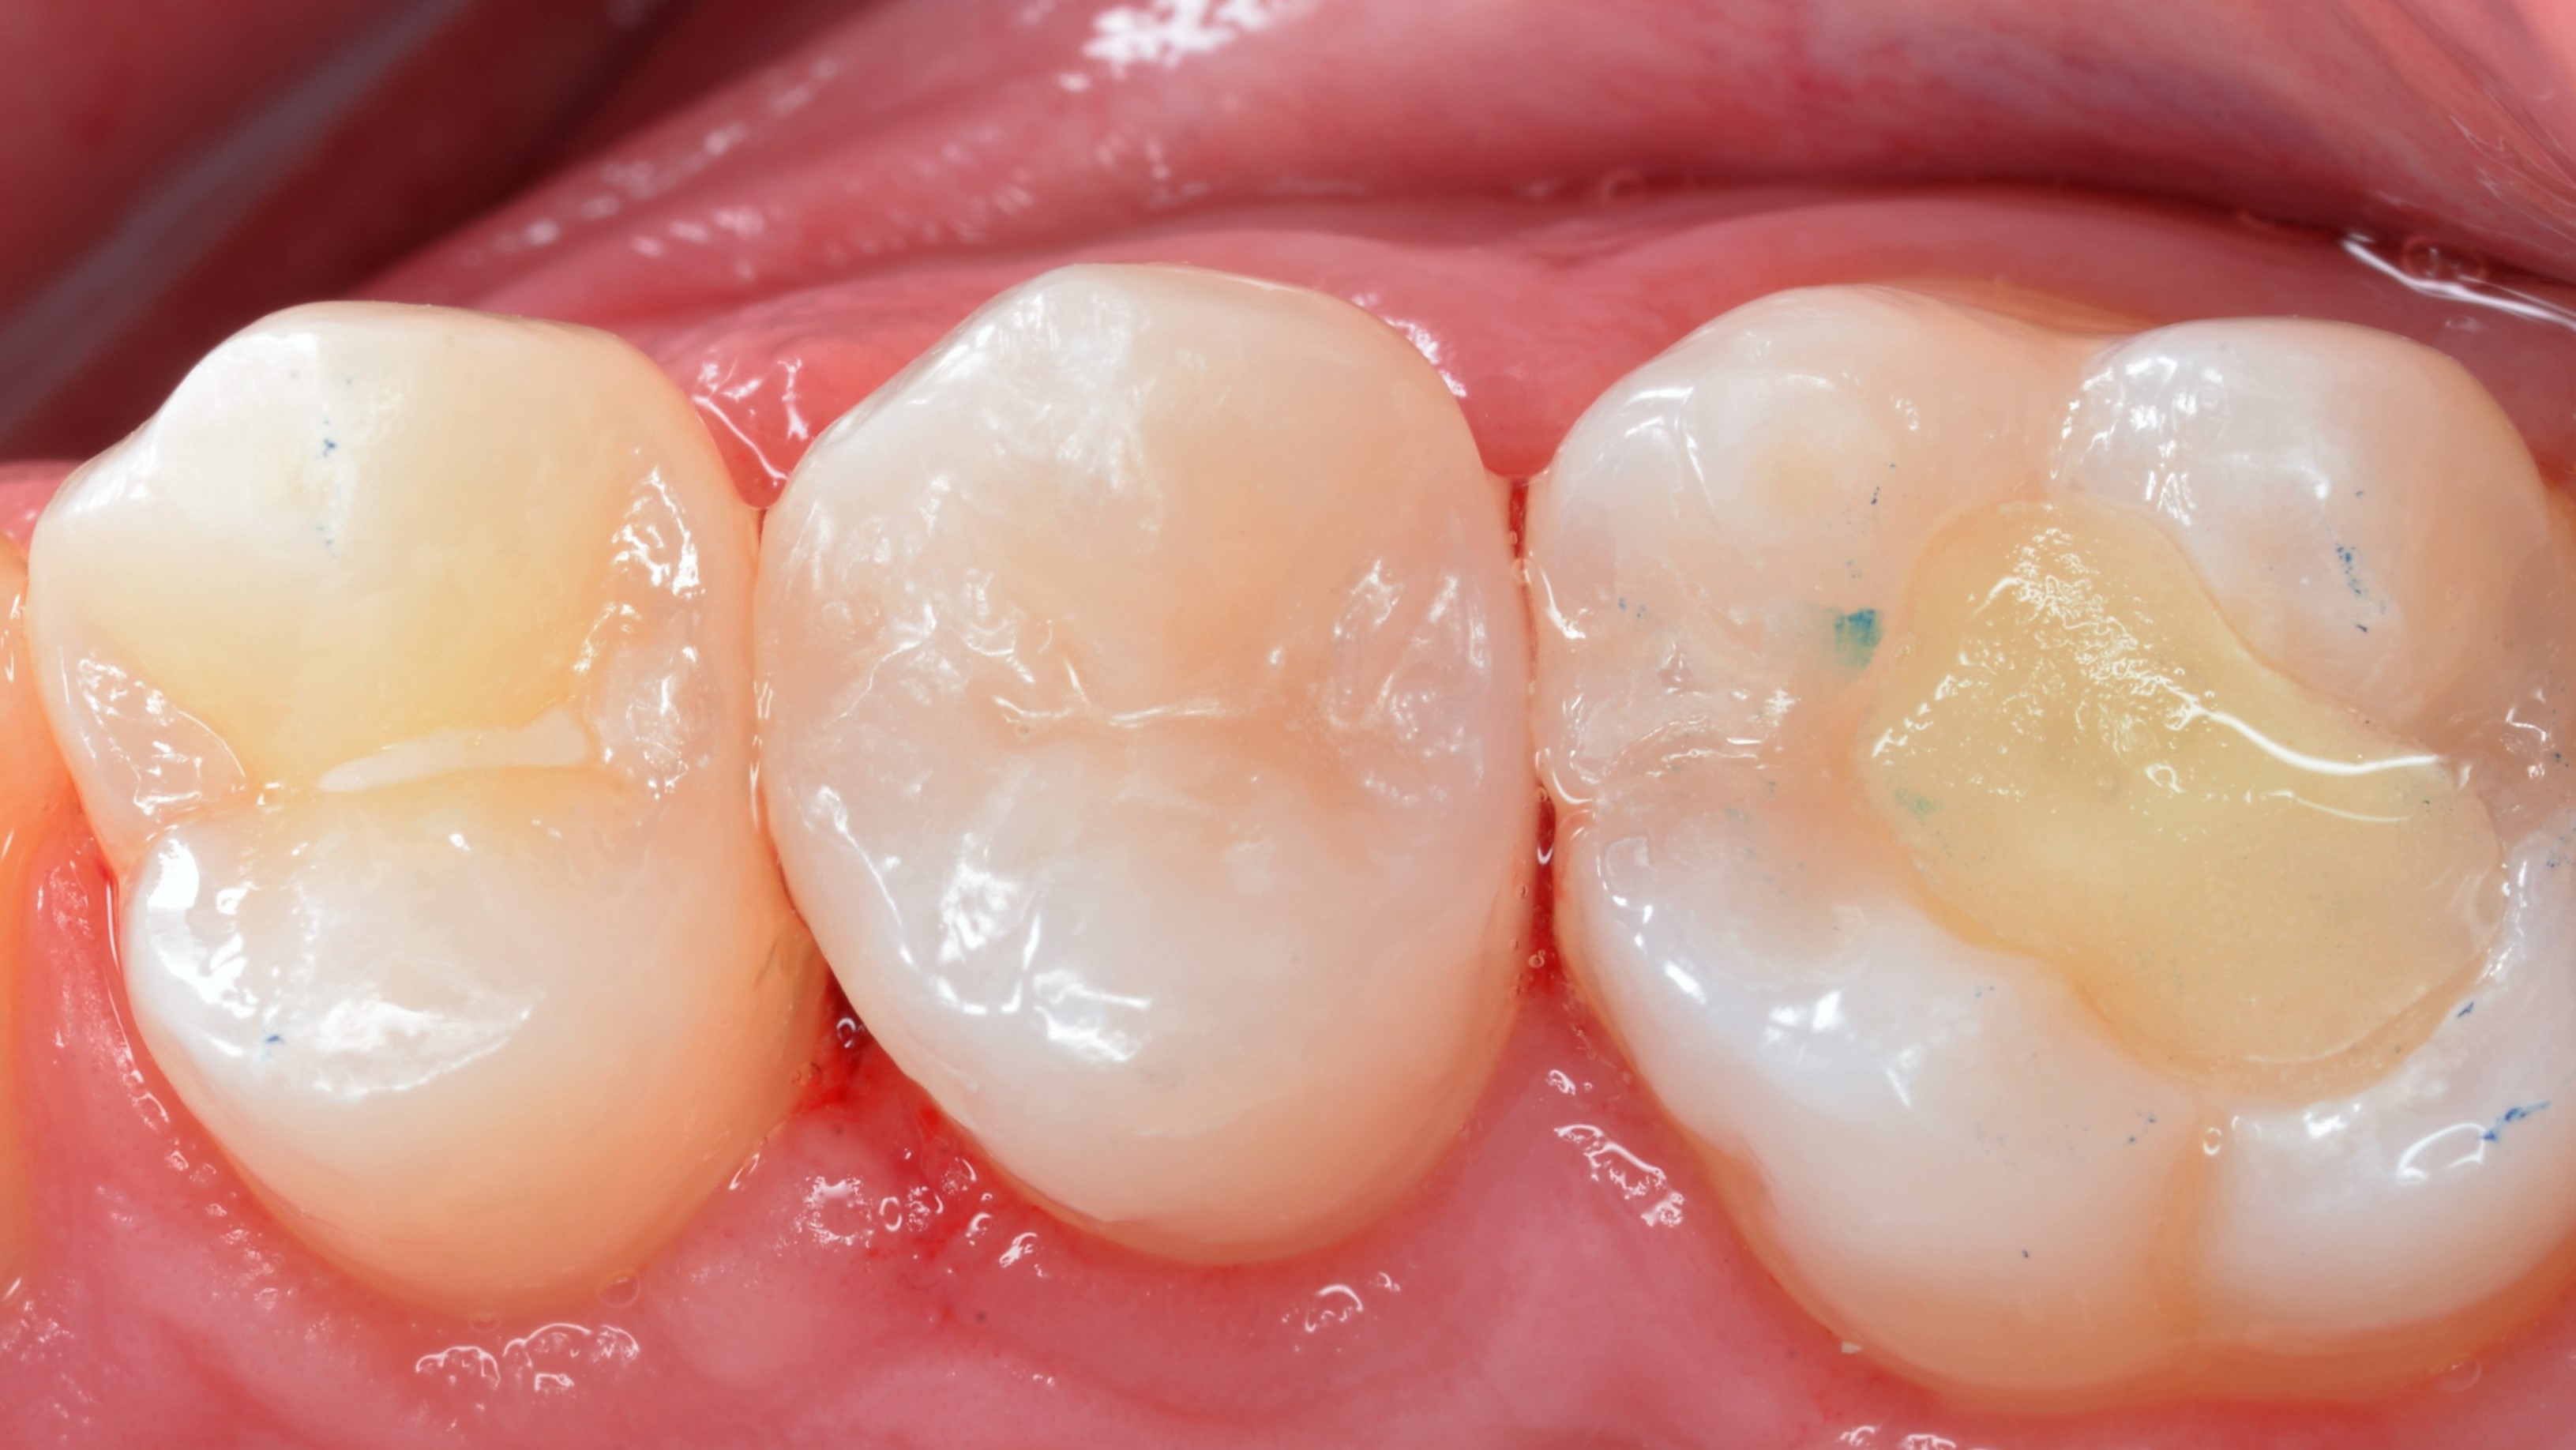

Wypełnienia wykończono dyskami ściernymi z nasypem z tlenku glinu (Sof-lex, 3M) oraz gumką impregnowaną węglikiem krzemu (BAL109F "brownie", Nevadent). Wstępne polerowanie wykonano gumkami diamentowymi Clearfil Twist DIA (Kuraray Noritake) oraz szczoteczkami nylonowymi (ryc. 9, 10). Odbudowy dostosowano w zgryzie i ostatecznie wypolerowano (ryc. 11, 12).

Ryc. 9. Wykończenie wypełnień (Sof-lex, 3M, BAL109F "brownie", Nevadent) i polerowanie wstępne (Clearfil Twist DIA, Kuraray Noritake, szczotka nylonowa).

Ryc. 10. Wykończenie wypełnień (Sof-lex, 3M, BAL109F "brownie", Nevadent) i polerowanie wstępne (Clearfil Twist DIA, Kuraray Noritake, szczotka nylonowa).

Ryc. 11. Stan po korekcie w okluzji i polerowaniu ostatecznym (Clearfil Twist DIA, Kuraray Noritake, szczotka nylonowa).

Ryc. 12. Stan po korekcie w okluzji i polerowaniu ostatecznym (Clearfil Twist DIA, Kuraray Noritake, szczotka nylonowa).